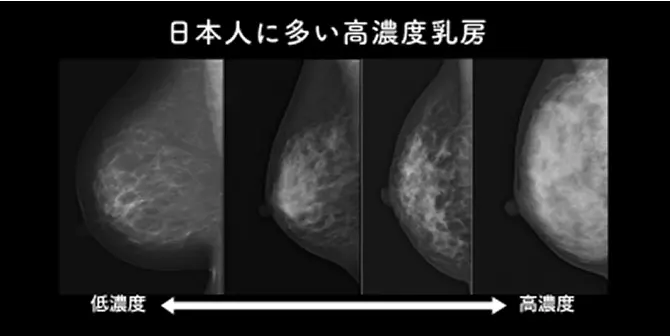

日本人の乳房に適している(高濃度乳房の影響を受けにくい)

無痛MRI乳がん検診では、乳腺の濃度の影響をほとんど受けないので、デンスブレスト(高濃度乳房)の方でも問題なく検査が可能です。